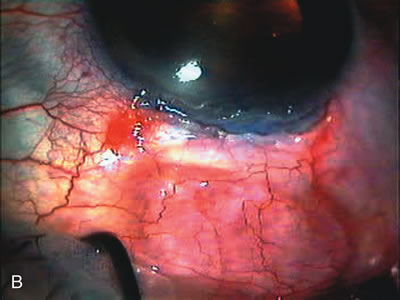

Fig. 3. Partial bleb failure following clear corneal phacoemulsification with foldable IOL. A. Preoperative bleb appearance prior to temporal lens extraction. Preoperative IOP was 12 mm Hg on no antiglaucoma medications. Time from 5-FU trabeculectomy surgery to lens extraction was one year. B. Bleb appearance 2 months after clear corneal cataract surgery with topical anesthesia. Following lens extraction, increased vascularity was noted along with decreased size of the filtering bleb. IOP increased to 20 mm Hg as early as 2 weeks after surgery, necessitating topical antiglaucoma therapy. C. High magnification view of bleb before lens extraction demonstrates diffuse pale bleb. D. High magnification view of bleb 2 months after surgery. There are vessels surrounding the nasal side of the bleb and the overall bleb size is smaller.

Cataract extraction by any technique performed in a patient with a pre-existing filter will have an effect on the previous filtering bleb.121–124 Bleb failure is more likely with ECCE compared with small-incision phacoemulsification.125 However, even patients undergoing topical anesthesia with clear corneal phacoemulsification and foldable IOL may experience bleb failure. One of three patients with a functioning filter and preoperative mean IOP of 12 mm Hg without antiglaucoma medications experiences bleb failure after lens extraction (Table 2). These patients require long-term drug therapy or bleb needling to control IOP. 126 Additional incisional glaucoma surgery may eventually be required in up to 10% of patients.127 Intraoperative iris manipulation may cause significant breakdown of the blood–aqueous barrier, resulting in inflammation that causes bleb failure. Even after uncomplicated clear corneal phacoemulsification, IOP may increase an average of 2 to 3 mm Hg due to bleb fibrosis.128 Approximately 20% of filtered patients require a long-term increase in glaucoma medications following uncomplicated clear corneal phacoemulsification with a foldable copolymer acrylic IOL129 (Fig. 3). In situations in which the bleb is not working at all, the eye will have a postoperative pressure spike that mimics that in the patient not having had a prior filtering procedure. In situations in which the bleb is marginal, the pressure spikes tend to be lower, and the final postoperative IOP tends to be around 50% higher than it was preoperatively. These patients require combined procedures in order to reestablish long-term filtration. In situations in which the bleb is very thin, polycystic, and associated with an IOP around 5 to 8 mm Hg on no antiglaucoma therapy; uncomplicated cataract extraction will have a minimal effect on the level of IOP. Patients with functioning glaucoma drainage implants usually have minimal long-term changes in IOP after uncomplicated cataract extraction.130